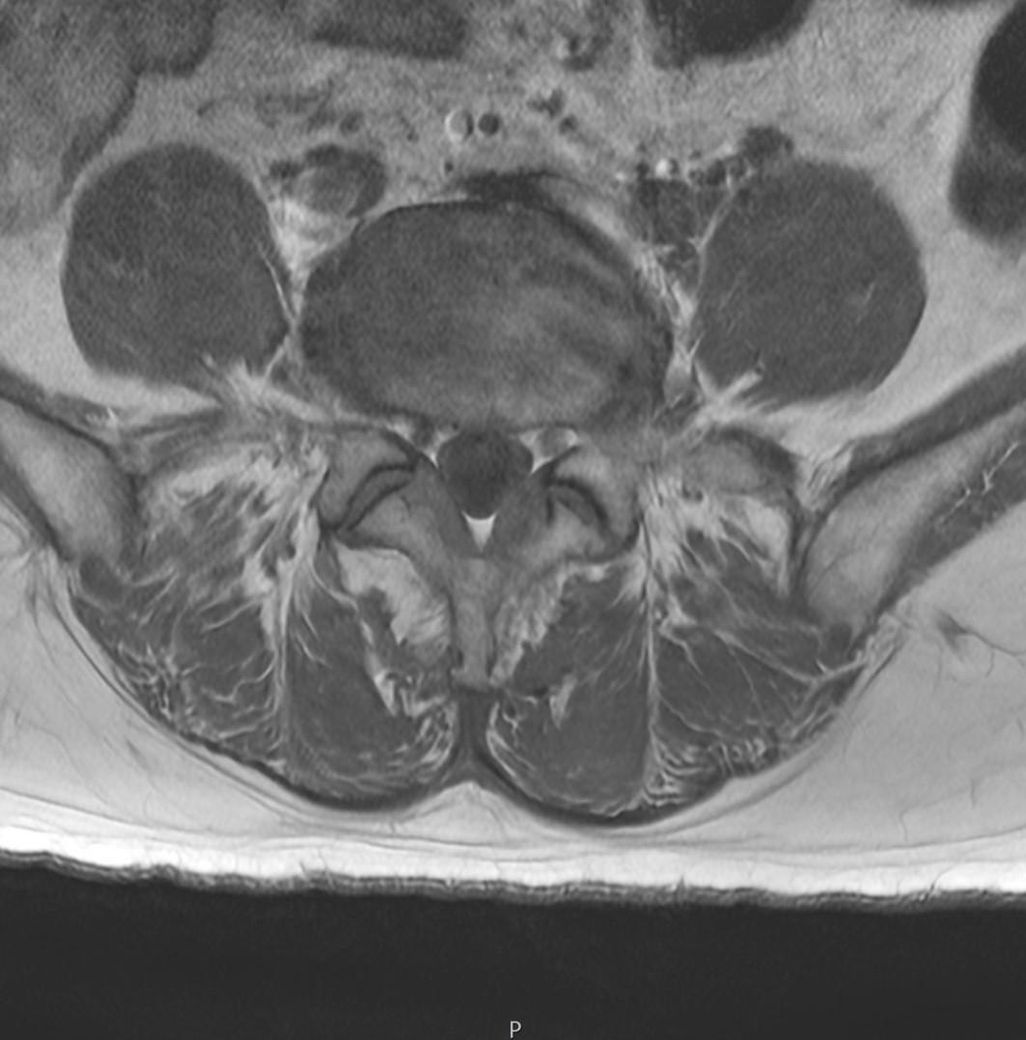

이거 디스크 맞나요? MRI 이미지있어요.

촬영한 이미지에요.

어느 위치인지 몰라요.

가운데 동그라미가 디스크라고 들었어요.

이미지의 오른쪽 아래가 퍼진것처럼 보여요.

혹시 터진 건 아니겠죠?

근육도 괜찮은지 봐주시면 감사하겠습니다.

디스크돌출 여부나 터짐을 확인하려면 전문의가 직접 mri영상을 확인하고 진단을 내려야 합니다. 근육 상태나 다른 이상이 있는지도 확인이 필요하므로 정형외과나 신경외과 전문의에게 mri결과를 가져가 상담을 받는 것이 좋아요!

공유해주신 사진상 정확한 상태를 확인하기는 어려우나 디스크의 큰 문제는 없는 것으로 보이며 자세한 진단 같은 경우 병원에 방문하시어 판독 받아보시는게 좋을 것으로 생각됩니다.

질문자분께서 첨부해주신 영상에서는 크게 신경 주변에 압박이 관찰되지는 않는데요, 이외에 통증이나 불편감이 느껴지시는 경우에는 치료가 필요할 수 있으므로, 전문의에게 진료를 통해 적절한 치료를 받아보시는 방법을 추천드립니다.